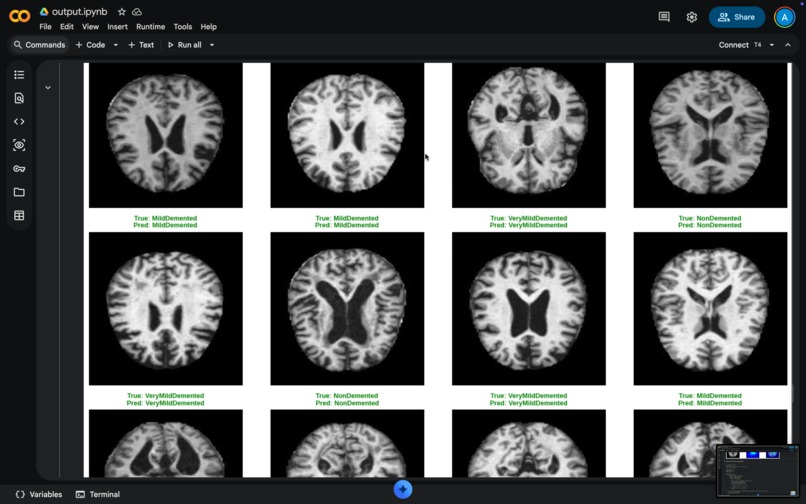

Our AI model classifies brain MRI scans into four stages of Alzheimer's disease progression:

Stage Label Description

🟢 NonDemented Healthy brain with no cognitive impairment

🟡 VeryMildDemented Very early stage — subtle changes detectable

🟠 MildDemented Mild cognitive impairment (MCI)

🔴 ModerateDemented Moderate-stage Alzheimer's disease